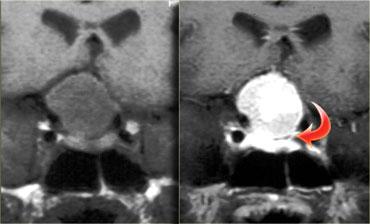

Bên trái là một ví dụ khác về u tuyến yên đại tuyến.

Tổn thương bắt đầu từ hố yên, vốn đã bị giãn rộng, và lan rộng vào bể dịch não tủy trên yên (suprasellar cistern).

Lưu ý hình ảnh ‘người tuyết’ kinh điển được tạo ra do sự thắt nghẽn bởi màng hoành yên.

Chú ý mức dịch-máu (blood-fluid level), cho thấy có xuất huyết.

Tầm quan trọng của việc quan sát hướng nghiêng của các lá màng hoành yên đã được đề cập trước đó.

Trên các hình ảnh chuỗi xung T2W bên phải, có thể thấy các lá màng hoành bị đẩy lên trên bởi khối u đại tuyến này, vốn bắt đầu từ hố yên và đang phát triển lên trên.

Một tổn thương có nguồn gốc từ phía trên hố yên và phát triển xuống dưới sẽ đẩy các lá màng hoành theo hướng ngược lại (điều này có thể thấy trong trường hợp u màng não chẳng hạn).